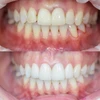

الدكتورة إسراء إيفيرجن ديميريورك طبيبة أسنان

طبيب أسنان